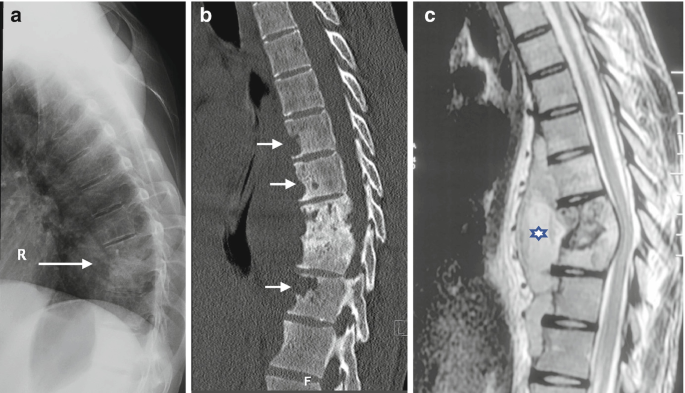

Pott's disease, another name for tuberculosis of the spine, is a severe type of skeletal tuberculosis that mainly affects the vertebral column. It is brought on by Mycobacterium tuberculosis, which enters the bloodstream from the lungs or other organs that are infected. As a result of TB spine, the vertebrae gradually deteriorate, resulting in stiffness, excruciating back pain, and occasionally spinal deformities or nerve compression. It can cause paralysis if untreated. Preventing irreversible spinal damage requires early diagnosis by MRI, CT scan, and biopsy. Most patients can recover completely and resume normal spinal function with prompt treatment. Therefore get in touch with us now because we have the Best Doctor for Tuberculosis (TB Spine) in Ghatkopar .

The severity of spinal tuberculosis determines how it is treated. The first step is medical management with anti-tubercular therapy (ATT), which usually lasts 9–12 months to completely eradicate the infection. Severe spinal instability, deformity, abscess formation, or neurological deficits necessitate surgical intervention. Instrumentation with rods or screws, spinal fusion to stabilize the affected vertebrae, and decompression to relieve pressure on the spinal cord are common procedures. Restoring spinal alignment, removing infected tissue, and avoiding neurological complications are the three main objectives of surgery. Based on imaging results and the patient's general health, treatment planning is customized for each patient. Visit to our clinic now and consult with the Best Doctor for Tuberculosis (TB Spine) in Ghatkopar.